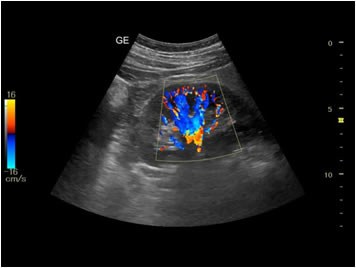

Testicular or scrotal scan is done to diagnose cause of pain or swelling in the testes such as inflammation or torsion and also to diagnose cause of infertility such as varicocele etc.